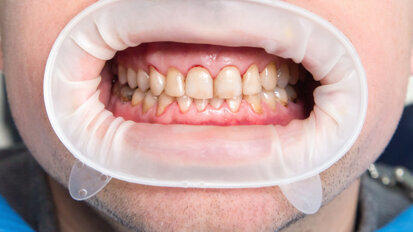

How to achieve aesthetic results with a completely digital workflow

In addition to many other specialties, the field of prosthodontics will be addressed in 3Shape’s upcoming 24-hour webinar marathon. Dr Jonathan Ng, who ...

Interview: “Minimally invasive dentistry is the better dentistry”

On 20 June, GC Europe will be holding its first international congress on minimum intervention (MI) dentistry. As an introduction, German-based dentist Dr ...

Four questions on current trends in direct posterior and anterior restorations

Dr Alexandra Papanikolaou owns a private dental clinic in Athens in Greece, focused mainly on restorative and aesthetic dentistry. In an upcoming webinar, ...